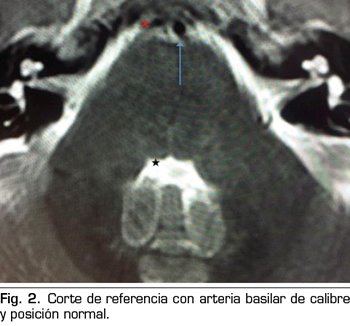

Presentamos el caso de un varón de 59 años, que cursa con un cuadro de parálisis del VI par craneal derecho, tras una cefalea postpunción dural, secundaria a una punción dural accidental durante una epidural. En la resonancia magnética, aparece un compromiso del espacio de la arteria basilar sobre la emergencia del VI par derecho. Posiblemente, esta variante anatómica vascular, lo haya predispuesto a una mayor vulnerabilidad del nervio abducens. La tracción del nervio, pudo producir una isquemia, convirtiendo a la hipotensión licuoral en el posible desencadenante de la parálisis. Con tratamiento conservador se recuperó completamente.

We present the case of a 59 years old man, who is diagnosed with a right sixth cranial nerve palsy, after the development of a dural post-puncture headache, secondary to an accidental dural puncture during an epidural. In magnetic resonance imaging, a compromise of the basilar artery space appears on the emergence of the right sixth cranial nerve. Possibly, this vascular anatomical variant, predisposed him to a greater vulnerability of the abducens nerve. The traction of the nerve could cause a neural ischemia, so intracranial hypotension could be the trigger of the palsy. He recovered completely with conservative treatment.